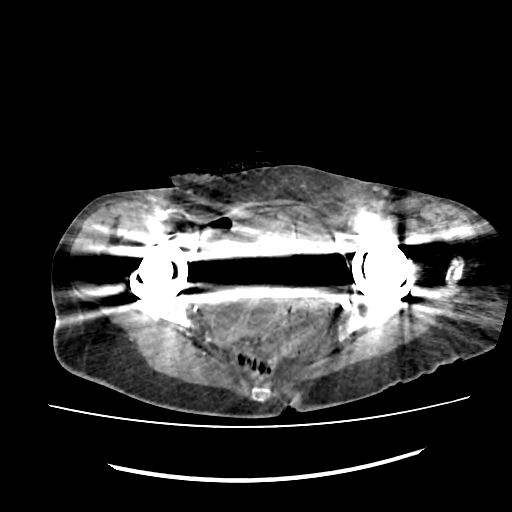

腹部环形伪影腹部环形伪影